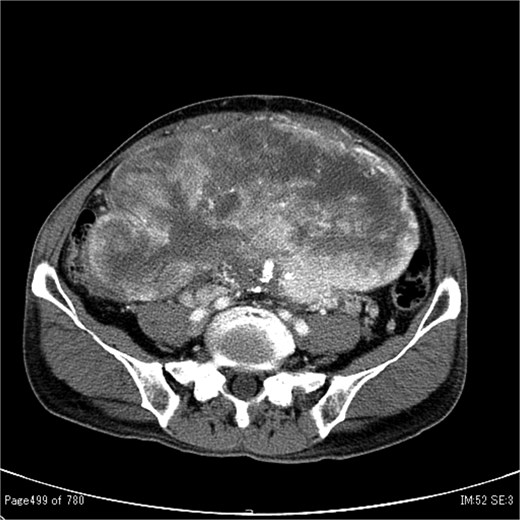

In 2011, a male patient in his 60s presented to the emergency department with loss of consciousness. His blood glucose level was 20 mg/dL. Contrast-enhanced computed tomography (CT) revealed a large tumour measuring 20 cm in diameter (Fig. 1). Primary surgery was performed and the tumour was diagnosed as an SFT histopathologically. Five years later, contrast-enhanced CT revealed a 4-cm tumour in the lower abdomen. His blood glucose levels were normal. A second surgery was performed; the tumour was excised, and several disseminated nodules were cauterized. Histology revealed that the tumour was an SFT. Eight years later, the patient presented with loss of consciousness. Laboratory data revealed a blood glucose level of 28 mg/dL. Contrast-enhanced CT revealed multiple tumours measuring 3–14 cm in diameter, spread within the abdominopelvic regions (Fig. 2). To prevent excessive intraoperative haemorrhage, preoperative TAE was performed on two larger tumours. Angiography revealed that the large tumour in the right lower abdomen was supplied by a branch of the superior mesenteric artery, whereas the pelvic tumour was supplied by branches from the inferior mesenteric and bilateral internal iliac arteries (Fig. 3). Super-selective catheterization and embolization of the vessels were performed. One week after embolization, a third surgery was performed. Nine tumours were resected. The operative time was 177 min, and the estimated blood loss was 620 mL. Histologically, part of the rectal wall showed necrosis. The tumour comprised spindle cells exhibiting a ‘patternless’ arrangement in a collagenous matrix (Fig. 4a). Immunohistochemical staining was positive for CD34, CD99, Bcl-2, and STAT6, which confirmed the diagnosis of recurrent SFT (Fig. 4b and c). The Ki-67 labelling rate was ~10% in the highly labelled regions. The tumour was also positive for insulin-like growth factor-II (Fig. 4d). After surgery, blood glucose levels completely stabilized. The patient developed a paralytic ileus that resolved spontaneously and was discharged 13 days after surgery. The patient was well, with no recurrence noted during the 10-month follow-up period.

Contrast-enhanced CT showing a large tumour measuring 20 cm in diameter occupying both the abdominal and pelvic cavities.